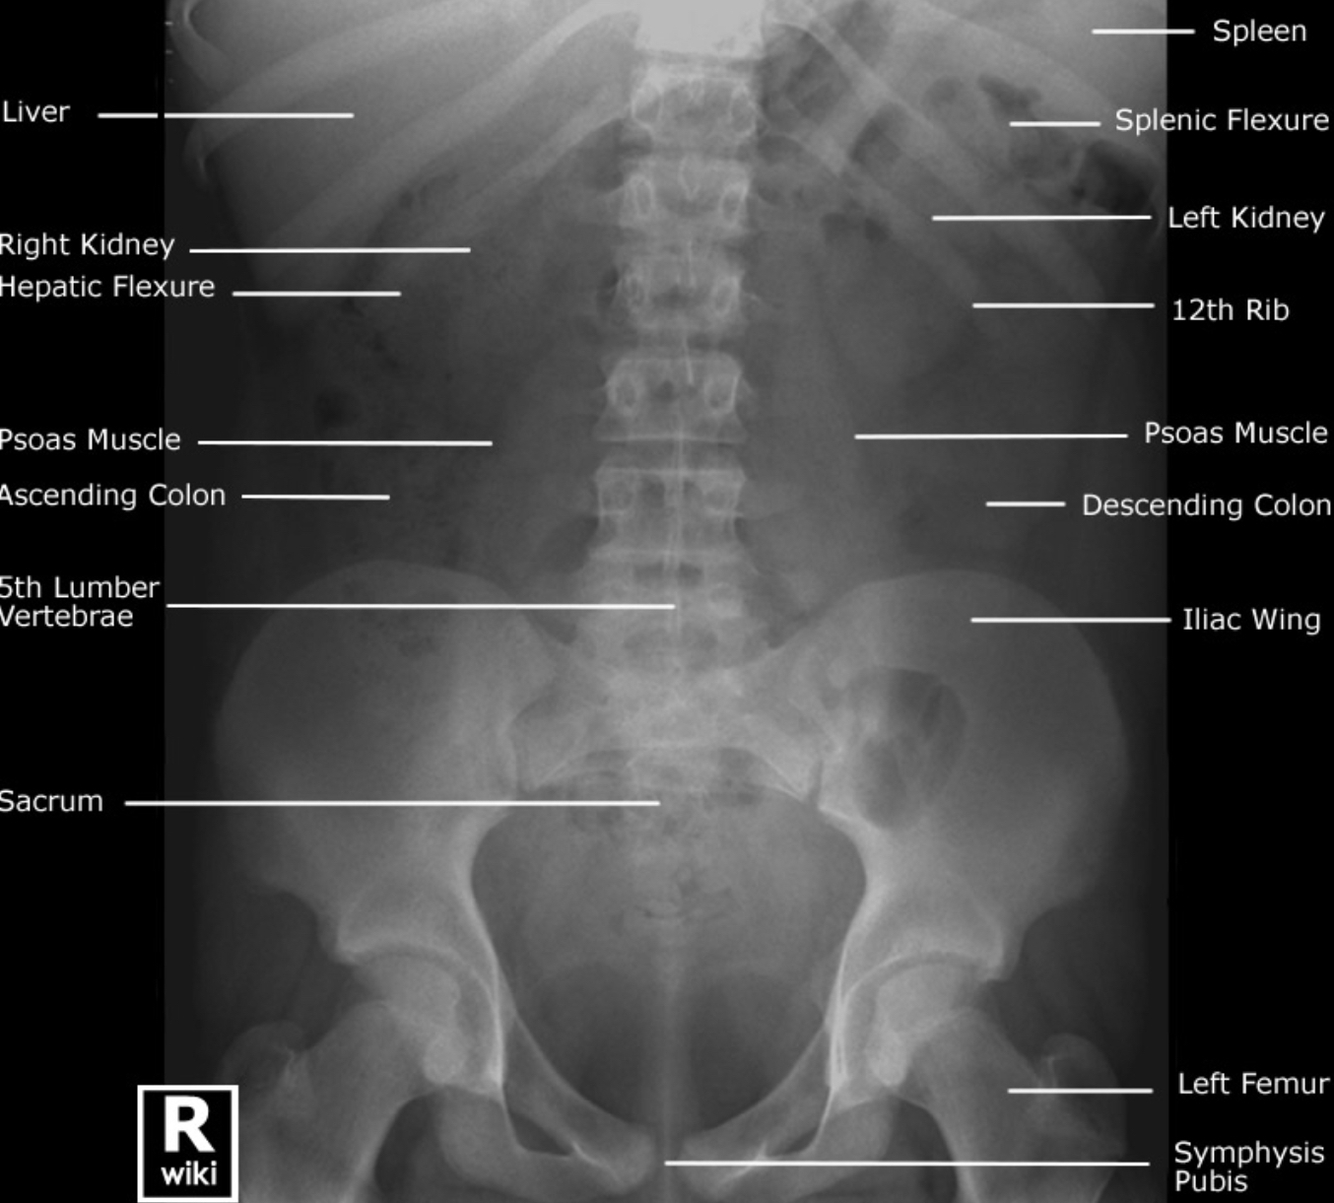

Label the viscera on the abdominal x-ray.